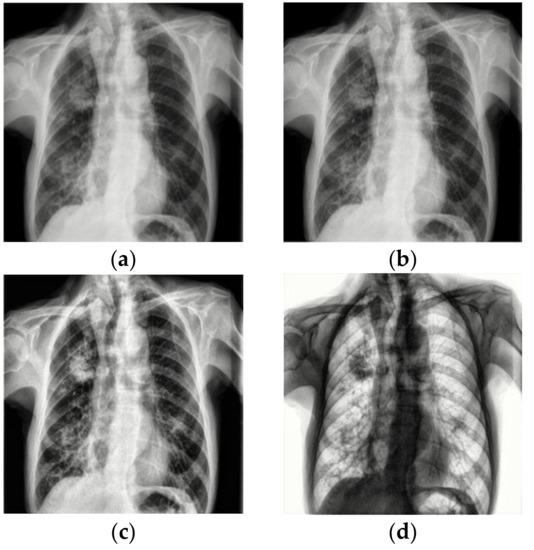

Although in Figure 1a,b the differences in lung health are obvious, with large white opacities in the infected lung, the differences between healthy lungs and lungs infected by COVID-19 are often much more subtle. Additionally, some other illnesses like pneumonia can appear similar in an X-ray to COVID-19, requiring intensive review to distinguish them from the latter virus. With cases drastically increasing each day, it can take a significant amount of time for doctors to analyze these X-rays that could be used for treating patients instead. Couple this with the tedious work of manually analyzing hundreds of images in a high stress environment and there is an even greater overburdening of doctors and risk of mistakes.

Figure 1.

X-rays of healthy and infected patients. X-rays from [7,8]. (a) Sample X-ray for healthy lungs. (b) Sample X-ray for COVID-19-infected lungs.